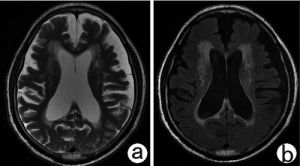

腦白質脫髓鞘

腦白質脫髓鞘,已經發育成熟的正常髓磷脂被破壞,即:腦白質脫髓鞘(demyelination)疾病。它主要包括:多發硬化、進行性多灶性腦白質病、急性散發性腦脊髓炎、亞急性硬化性全腦炎、橋腦中央髓鞘溶解症、胼胝體變性、皮層下動脈硬化性腦病和同心圓硬化等。

腦白質內可發生許多疾病。而腦白質對各種有害刺激的典型反應是脫髓鞘變化,它可以是神經系統疾病如感染、中毒、退行性變、外傷後、梗塞缺乏等的繼發表現。有一組至今原因尚不甚明確的中樞神經系統脫髓鞘性疾病。因此,目前對這一組疾病的分類,按它們起病時賄鞘發育是否成熟,可將這組疾病分為兩個大類:①髓鞘發育正常的脫髓鞘性疾病,如多發性硬化、進行性多灶性腦白質病、急性散發性腦脊髓炎等;②髓鞘形成不良性疾病,如類球狀細胞型腦白質營養不良、異染性腦白質營養不良、海綿狀腦病等。